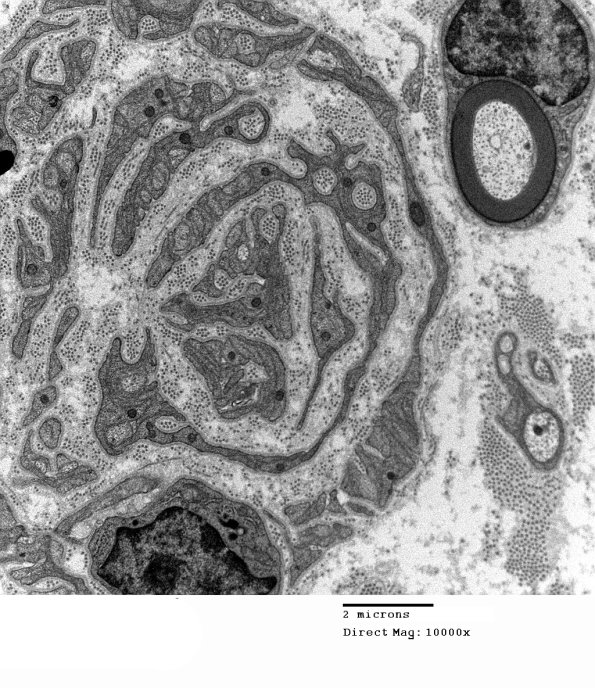

6C2A,B These collagen pockets are present in increased numbers which is evidence of unmyelinated axon degeneration, (electron micrographs)